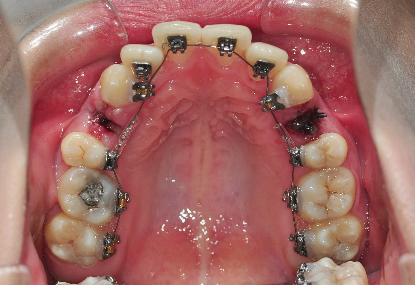

상악에 치아교정 장치 부착도 하악과 마찬가지로

일단 치석을 제거하고 깨끗하고 건조하게 치아를 만들어주었어요~

그리고 나서 접착제로 브라켓과 고무를 치아에 끼워넣어 부착하고

고무를 제거하면 치아교정 장치 부착 끝~!!

치아교정 장치를 부착한 다음, 철사를 연결합니다~

어떤 부분은 투명한 관에 철사를 넣어 연결해 주시는데요~

미니똑딱이브라켓이라 브라켓을 핀셋으로 여시고 철사를 넣으시고 닫으시는 것 같았어요 ^^*

이로써 치아교정 장치 부착은 상악, 하악 다 이루어졌어요 ^.^